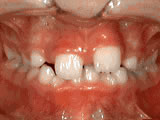

Phase-One

Patient's parents were concerned about both aesthetics and the health of the erupting permanent teeth when they brought him to the orthodontist at age eight. The lower front teeth were crowded and touching the palate, and the upper front teeth were extremely displaced from their normal positions. After 12 months of Phase-One treatment with an expander and partial braces, patient's appearance and dental function were vastly improved.